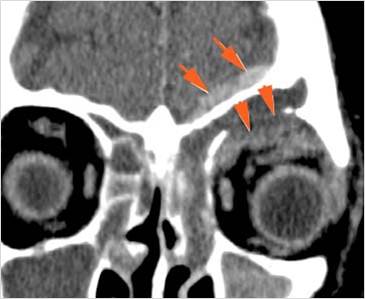

There is fracture of the greater or lesser wing of the sphenoid bone, optic strut and canal, or basisphenoid, in the region of the orbital apex.

The circumferential extraconal and the intraconal orbital fat including that of the orbital apex are edematous or otherwise abnormal.